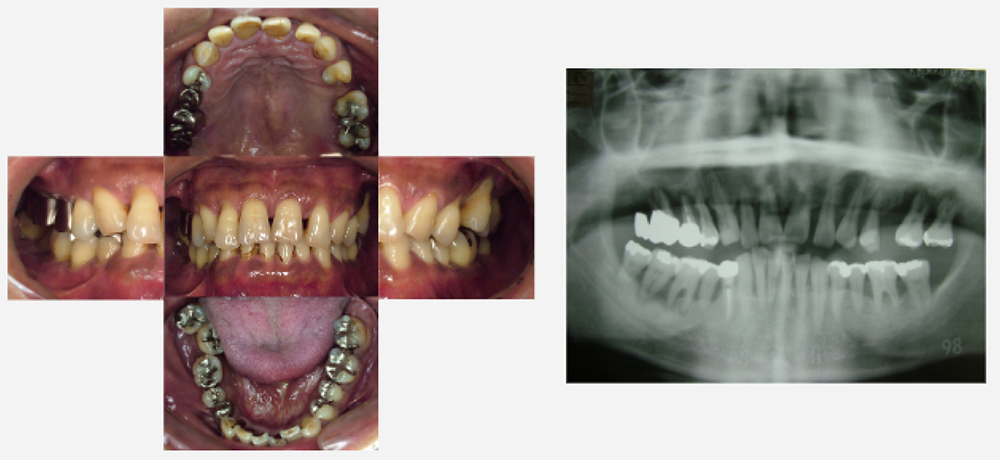

治療前治療後

| 治療内容 | インプラント奥歯1本 |

|---|---|

| 患者様の年齢 | 48歳 |

| 患者様の性別 | 男性 |

| 治療期間 | 5ヶ月 |

| 治療回数 | 25回程度 |

| 治療費用 | 50万円 |

| 治療で得られるメリット |

|

| 治療する際に起こる リスク・副作用 |